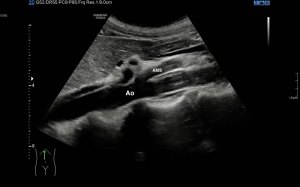

Si colocas la sonda en el mentón, en axial vas a encontrar este músculo Digástrico, que se verá muy bien, superficial, en un plano intermedio tendrás el músculo Milohiodeo y en la profundidad los músculos Geniohideos, Geniogloso y el Hiogloso…Mira:

El Músculo Milohioideo se encuentra en un plano medio, es fino y separa el plano superficial muscular, del profundo, en la imagen superior ves una pequeña porción de este músculo. En el plano profundo un grupo de varios músculos, que he mencionado más arriba y que son músculos extrínsecos de la lengua, situados en la región más medial de esta localización submentoniana estudiada.